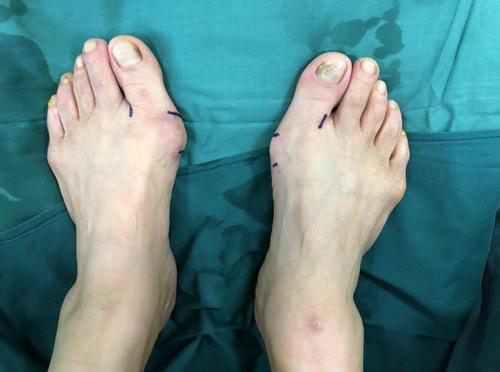

家住贾汪区的李大姐,20年前发现双足踇外翻畸形,行走时疼痛,但一直未予重视,8年前畸形加重,在徐州某家医院做了踇外翻手术,治疗后效果不好,近几个月疼痛逐渐加重。

术前X线

3月11日上午,我院石荣剑院长为她做过体检和相关影像检查后,考虑患者二次手术,恐惧开大切口,决定为患者实施微创踇外翻矫正术。